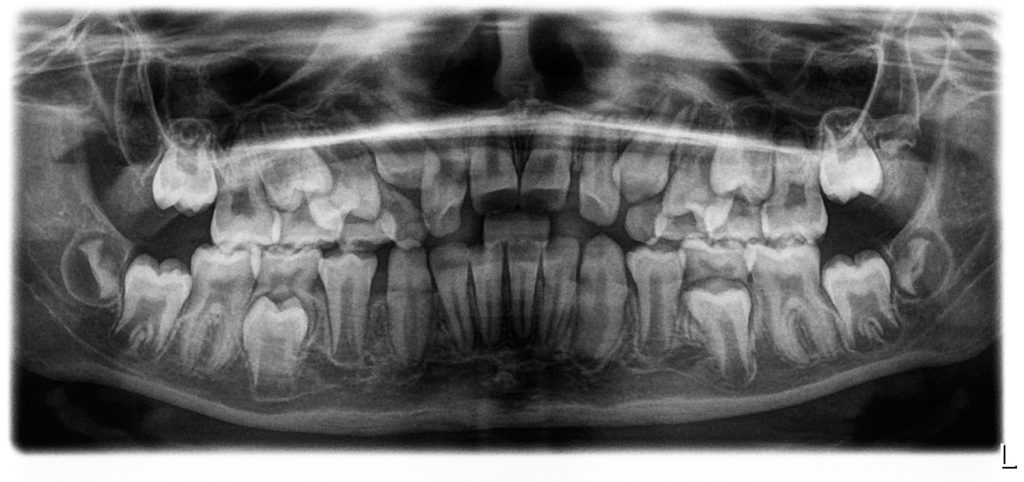

Through clinical tests and radiographs, we explored whether Amaira’s mouth breathing was due to physical blockage or an acquired habit.

Key Findings

- Narrow upper jaw (palate)

- Open bite with dental spacing

- Lip incompetence at rest

- Habitual mouth breathing pattern

- Enlarged adenoids without full obstruction